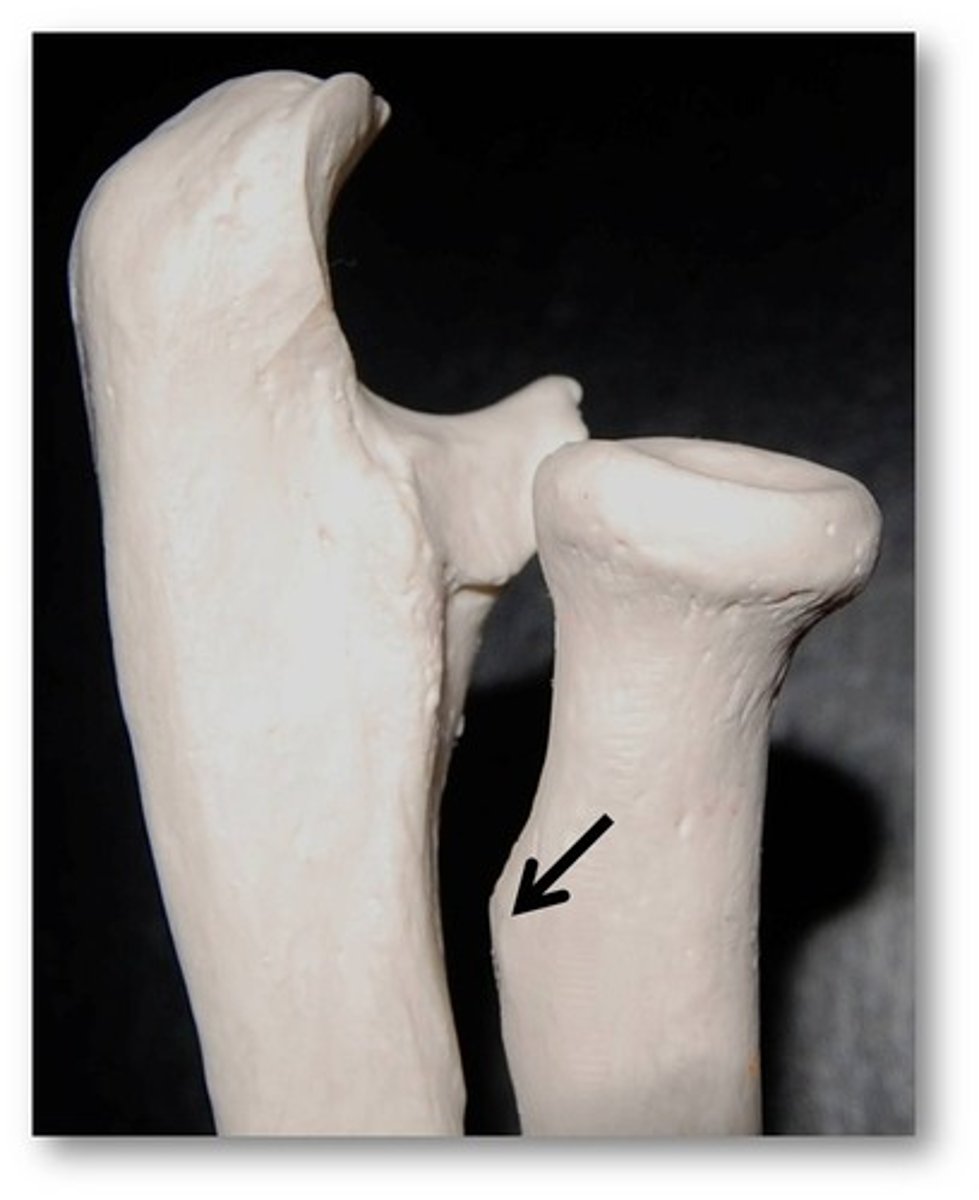

Lesser trochanter

Name this specific part of the femur.

Lesser trochanter

Name this specific part of the femur.

Neck

Name this specific part of the femur.

Neck

Name this specific part of the femur.